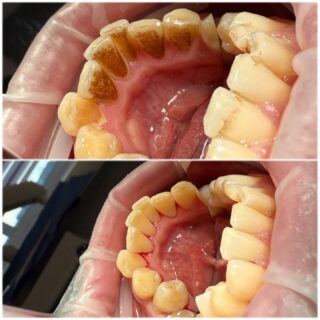

• 🦷 Higienizacja w gabinecie stomatologicznym — fundament zdrowia

Regularna higienizacja jamy ustnej to nie zabieg kosmetyczny, lecz procedura medyczna, która realnie wpływa na zdrowie całego organizmu.

Kamień nazębny jest rezerwuarem bakterii.

Bakterie z jamy ustnej mogą przedostawać się do krwiobiegu i krążyć po organizmie.

Nieleczony kamień prowadzi do zapalenia dziąseł i chorób przyzębia, a w konsekwencji do rozchwiania i utraty zębów.

Na czym polega higienizacja?

✔️ skaling – usunięcie kamienia naddziąsłowego i poddziąsłowego

✔️ piaskowanie – usunięcie osadów i przebarwień

✔️ polerowanie – wygładzenie powierzchni zębów

✔️ (opcjonalnie) fluoryzacja

Czym jest piaskowanie zębów?

To zabieg polegający na oczyszczaniu zębów strumieniem wody, powietrza i drobnego proszku. Skutecznie usuwa osady po kawie, herbacie czy papierosach, docierając tam, gdzie nie sięga szczoteczka.

Zdrowie + estetyka

Po higienizacji zęby stają się gładsze i optycznie jaśniejsze, a oddech wyraźnie świeższy.